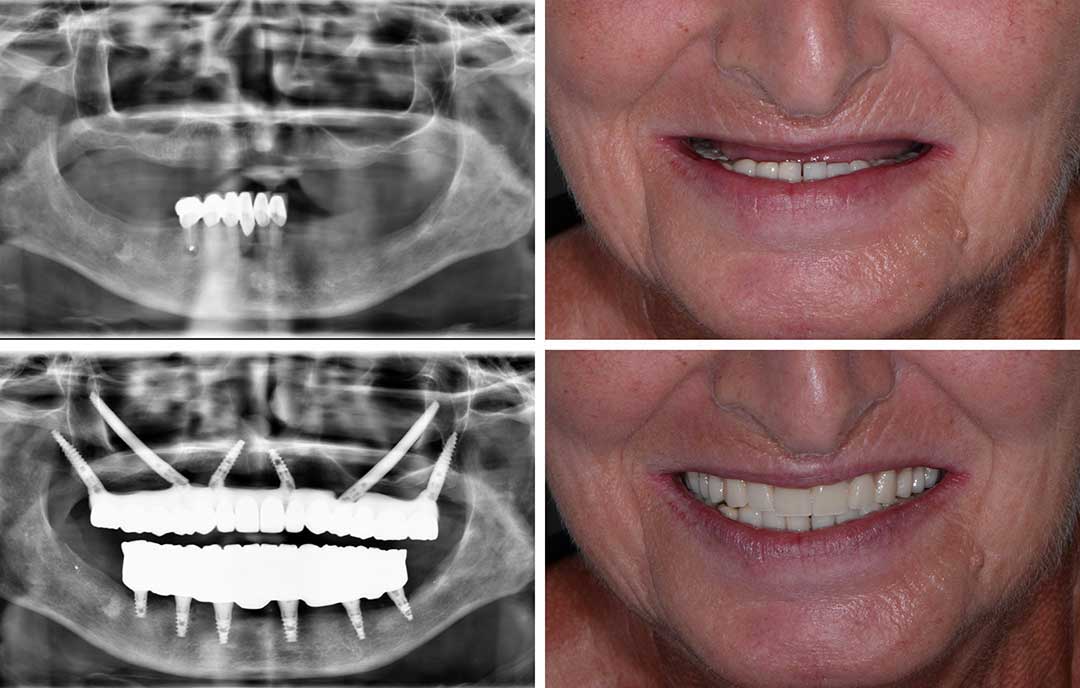

Ausgangssituation

Ein 81-jähriger Patient mit maximaler Atrophie im Ober- und Unterkiefer. Der fortgeschrittene Knochenverlust ließ eine herkömmliche Implantation nicht mehr zu.

Lösung

Im Unterkiefer wurde eine navigierte Full-Arch-Rekonstruktion mit speziellen Implantaten durchgeführt. Rechts erfolgte eine Quad-Zygoma-Operation. Der Patient erhielt direkt postoperativ eine provisorische, verschraubte Brücke.

Vorteile

Möglichkeit einer sicheren Sofortversorgung trotz extremer Atrophie

Vermeidung ausgedehnter Knochentransplantationen

Wiederherstellung der Kaufunktion sowie eines stabilen und ästhetischen Lächelns